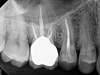

(1.) Preoperative CBCT scan showing Class 2 ECR defects on teeth Nos. 3 and 4 that were surgically accessible.

Figure 1

(2.) NSRCT, which had previously been completed on tooth No. 3, was also completed on tooth No. 4 prior to initiating surgical repair of the ECR lesions because it exhibited signs and symptoms of irreversible pulpitis.

Figure 2